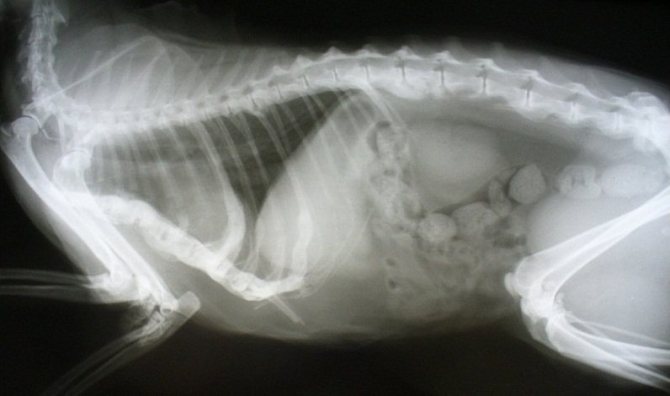

Рентген почек у кошки, страдающей мочекаменной болезнью